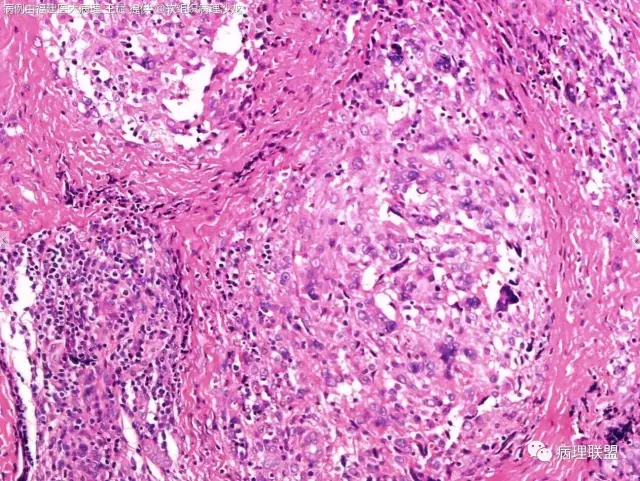

38岁,女性,手部小指背侧皮下肿物,3×2cm(病例由福建医大病理 王斌提供,致谢!)

血管瘤样纤维组织细胞瘤的肿瘤周围有淋巴细胞鞘,结节状分布,有假包膜,出血囊性变的为其主要特点,当然少数病例可以没有出血囊性变却出现粘液变。肿瘤细胞有一定异形性,属于低度恶性或交界性,最好做个FISH,看看有没有EWSR1-CREB1融合基因,刚查了一下,血管瘤样纤维组织细胞瘤还有另一种EWSR1-ATF1融合基因,无论是哪种,用EWSR1分离探针就可以检测